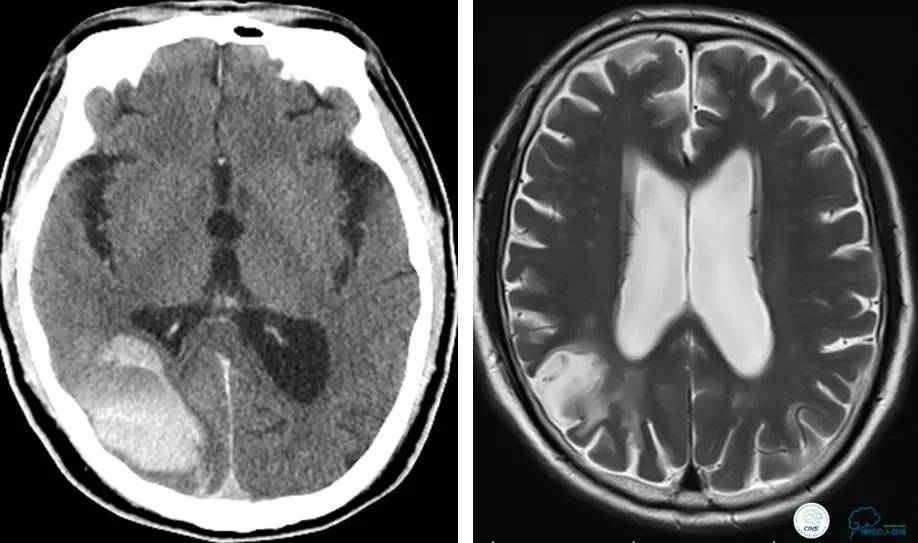

▼术后即刻CT,梗死灶内再灌注出血。

患者无症状,中性治疗。4月21日电话随访,一般情况好,当地CT示出血吸收期。

术后即刻和6天后CT,患者无明显临床症状。

半年后复查造影,无支架内再狭窄,可见弹簧圈,患者恢复至自己柱杖行走。